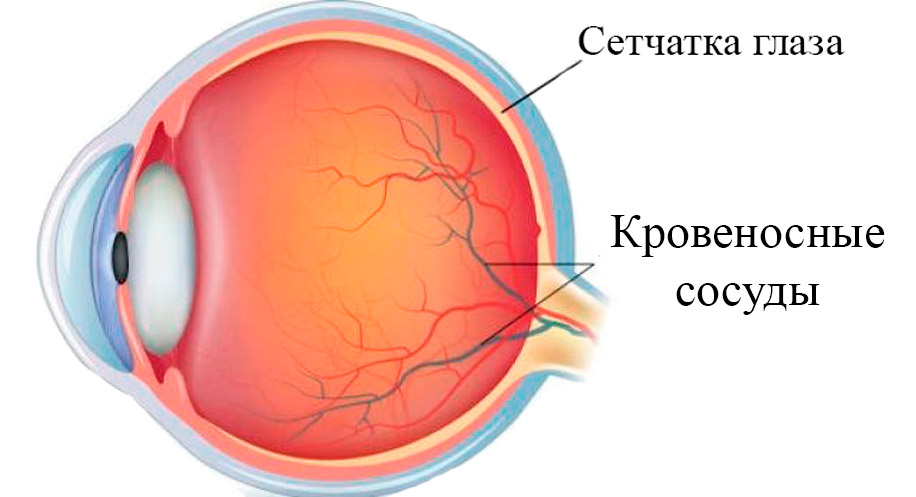

Изображения и анатомия сетчатки глаза